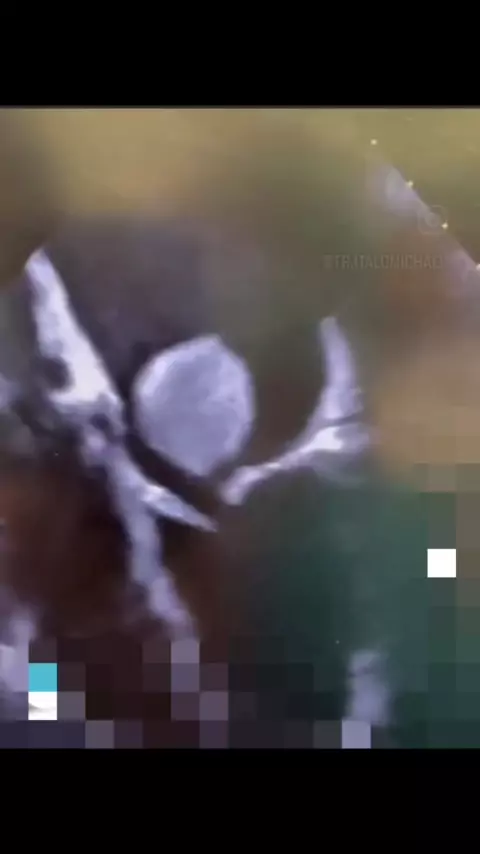

fala radiologista tudo bem? Eu me chamo Italo Michael sou técnico em radiologia E hoje vamos falar sobre ecocardiograma. a imagem em questão apresenta uma imagem arredondada no átrio esquerdo que pode corresponder a um trombo (coágulo)que está dentro do átrio esquerdo. Lembrando que quem fecha o diagnóstico são os médicos não sou eu técnico e nem os tecnólogos em radiologia ,o exame apresentado é de responsabilidade dos médicos cardiologista.